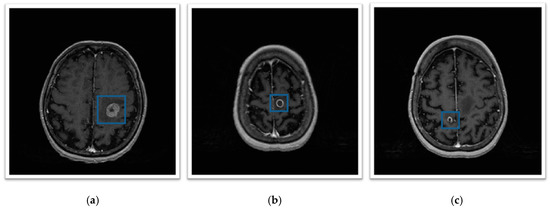

The acquired dataset is composed of 45 T1c volumetric MR scans. Volumes are acquired using a 3D sequence characterised by 0.9 mm isotropic voxels, the pixel spacing of 0.47 mm and the slice thickness of 2.67 mm. The tumour cases considered are heterogeneous in terms of shape, position and intensity level (see Figure 6).

Figure 6. (ac) Show three source slices of T1c MR Volumes with the delimitation of the lesion area.